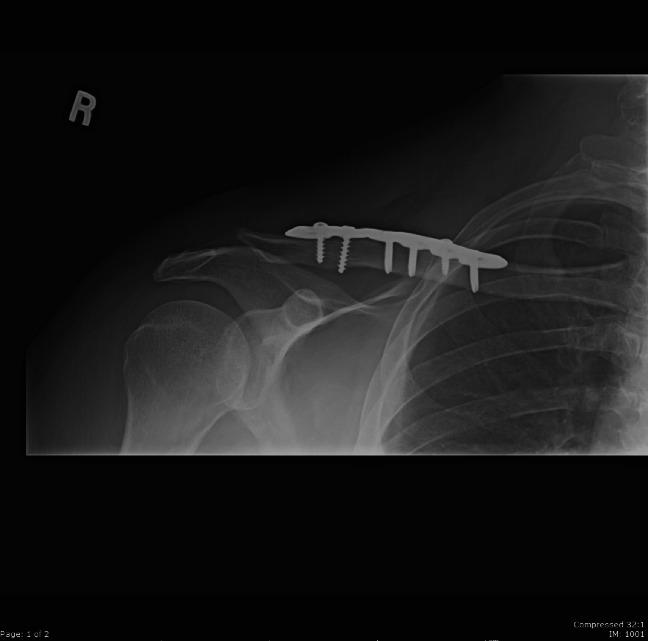

Clavicular eosinophilic granuloma causing adult shoulder pain.

Rare Tumors. 2013 Mar 1;5(1):e8. doi: 10.4081/rt.2013.e8. Print 2013 Feb 11.